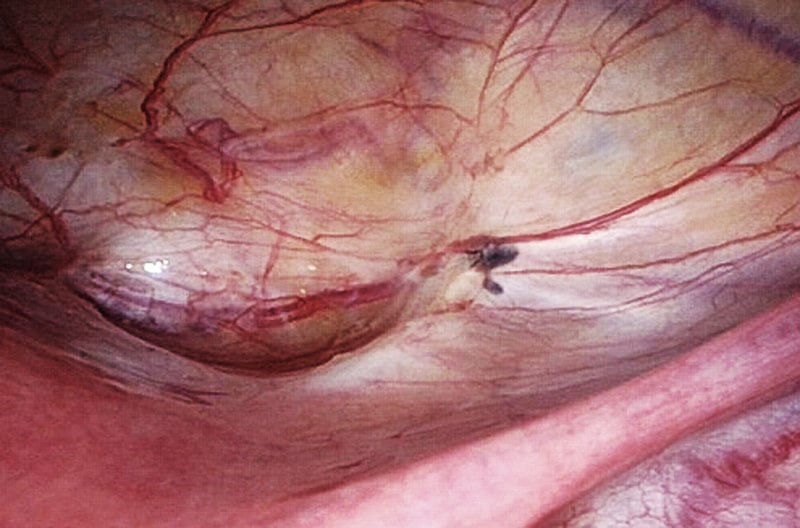

Bei der Endometriose tritt Gewebe, das dem der Gebärmutterschleimhaut (lat. Endometrium) ähnelt, im Unterleib außerhalb der Gebärmutter auf und siedelt sich auf verschiedenen Organen ab, z.B. auf Gebärmutter, Bauchfell, Eileitern, Eierstöcken, Blase oder Darm. In sehr seltenen Fällen sind auch andere Organe betroffen, wie z.B. die Lunge.

In den meisten Fällen werden diese Endometrioseherde von den Hormonen des Monatszyklus beeinflusst. So können die Herde zyklisch wachsen und bluten. Die Folge sind Entzündungsreaktionen, die Bildung von Zysten und die Entstehung von Vernarbungen und Verwachsungen im Bauchraum. Dies kann sich in zeitlicher Abhängigkeit vom Menstruationszyklus in den schmerzhaften Symptomen zeigen. Endometriose ist außerdem eine der häufigsten Ursachen für Unfruchtbarkeit. Aber: